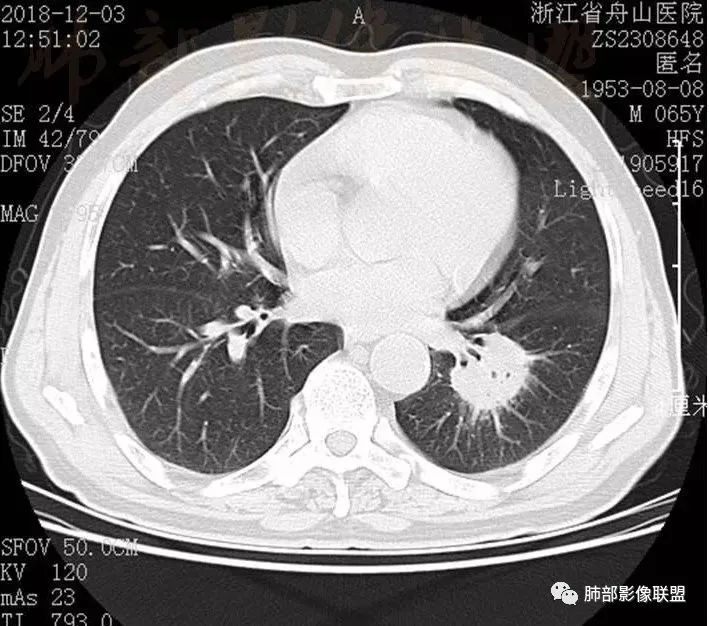

淋巴瘤为一组原因不明的累及全身淋巴网状系统的以淋巴组织过度增生为特征的恶性免疫细胞性肿瘤,病理上分为非霍奇金淋巴瘤(NHL)和霍奇金淋巴瘤(HL);肺内淋巴瘤是指淋巴瘤的肺内浸润,总共有4种:原发性肺淋巴瘤(PPL)、继发性肺淋巴瘤(SPL)、获得性免疫缺陷综合征相关淋巴瘤及移植后淋巴增值性疾病。

原发性肺淋巴瘤(PPL)是指肺实质或支气管的淋巴组织异常增生,侵犯的主要对象就是肺间质和支气管粘膜下组织,无纵膈、肺门及其他部位的淋巴瘤,在发病时或者确诊后3个月内没有肺外病变的证据,是结外肺淋巴瘤的一种罕见类型,以肺的非霍奇金淋巴瘤(NHL)多见,其中NHL肿最常见的就是结外边缘区黏膜相关淋巴瘤组织(MALT)淋巴瘤,其次是弥漫大B细胞淋巴瘤。

肺内淋巴瘤的影像学表现形式各样,总共有五种类型,⑴结节肿块型、⑵肺炎肺泡型、⑶间质型(支气管血管淋巴管型)、⑷粟粒型、⑸混合型(多种形态并存),不过小编认为分型只是对于病灶形态的描述,很多情况下多种类型并存,其中粟粒型分型比较少见。

多发结节、肿块型---肺淋巴瘤样肉芽肿

1.病灶分布:因为肺内淋巴瘤主要侵犯对象是肺间质和支气管黏膜下组织,病灶主要位于在沿支气管血管束分布、肺间质及胸膜下,病灶可跨叶分布。